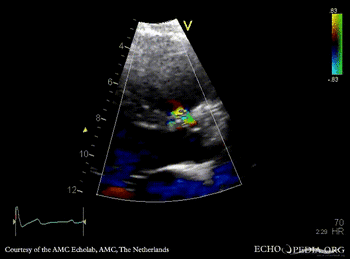

PLAX with Color Doppler Continuous-wave Doppler signal of flow through ventricular septum defect